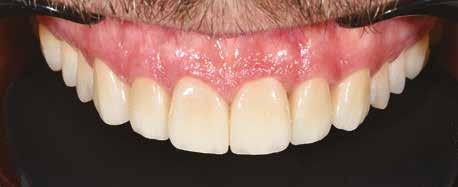

A 26 éves férfi páciens azzal a kéréssel kereste fel a rendelőnket, hogy a frontfogai esztétikusabb megjelenését szeretné elérni. A páciens jó általános egészségi állapottal rendelkezett, nem szenvedett allergiáktól és nem kellett rendszeresen gyógyszereket szednie. A páciens lehetőség szerint kerülte a fogai megmutatását. Rendkívül zavarónak találta a nagymetszői között, a középvonalnak megfelelően látható rést, a fogain látható kopási jeleket, valamint a fogai méretét is túl kicsinek találta. A szájüregi vizsgálat során megállapítottuk, hogy a nagymetsző fogai (11, 21) élharapásban vannak, valamint az alsó fogíven kismértékű torlódást észleltünk. A felső frontfogakon

(13-23) attrícióra utaló jeleket találtunk. A fogak kopása a nagymetszőfogaknak megfelelően volt a legkifejezettebb (1. ábra) . Az előbbiekben említett fogak (11, 21) ezen kívül némileg elfordultak, és jelentősebb méretű diasztéma volt köztük. A páciens Angle I.-osztályú állcsontrelációs helyzettel rendelkezett. A vizsgálat során feltűnt, hogy a páciens csak nagyon óvatosan mert mosolyogni (2. ábra)

A szájüregi vizsgálat során nem találtunk szuvas léziók jelenlétére utaló eltéréseket. A nagymetszőfogakon megfigyelhető jelentős mértékű kopás ellenére nem észleltünk craniomandibuláris diszfunkció jelenlétére utaló jeleket. A vizsgálat befejezését követően a pácienst tájékoztattuk a különböző kezelési lehetőségekről. Az esztétikai megjelenés javítása érdekében először egy alignerekkel végzett fogszabályzó kezelés elvégzését, majd a harapási helyzet optimalizálását követően a felső frontfogai kompozittal történő direkt felépítését vagy héjakkal történő ellátását (pl.: non-prep héjak) javasoltuk (3. és 4. ábra).

A páciens teljesen elégedett volt a kezelések befejezését követően elért esztétikai végeredménnyel (9. ábra). A terápiás erőfeszítéseink eredményeinek köszönhetően újra képes felszabadultan nevetni és mosolyogni. A cikkben bemutatásra kerülő eset jól példázza a multidiszciplináris beavatkozások alkalmazásában rejlő előnyöket. A megfelelő sorrendben végzett orthodonciai és restauratív kezelésekkel lehetővé vált a páciens mosolyának minimálinvazív módszerekkel történő optimalizálása. A körültekintő tervezésnek köszönhetően nem került sor felesleges beavatkozások elvégzésére, és emiatt a kezelések befejezéséhez szükséges idő sem nyúlt a szükségesnél hosszabbra. Arra is felhívnánk a figyelmet, hogy a jól megszervezett, továbbá a lehető legkevesebb rendelési időt felhasználó kezelések – a beavatkozásokat végző fogorvosok számára is – rendkívül kedvezőek lehetnek.